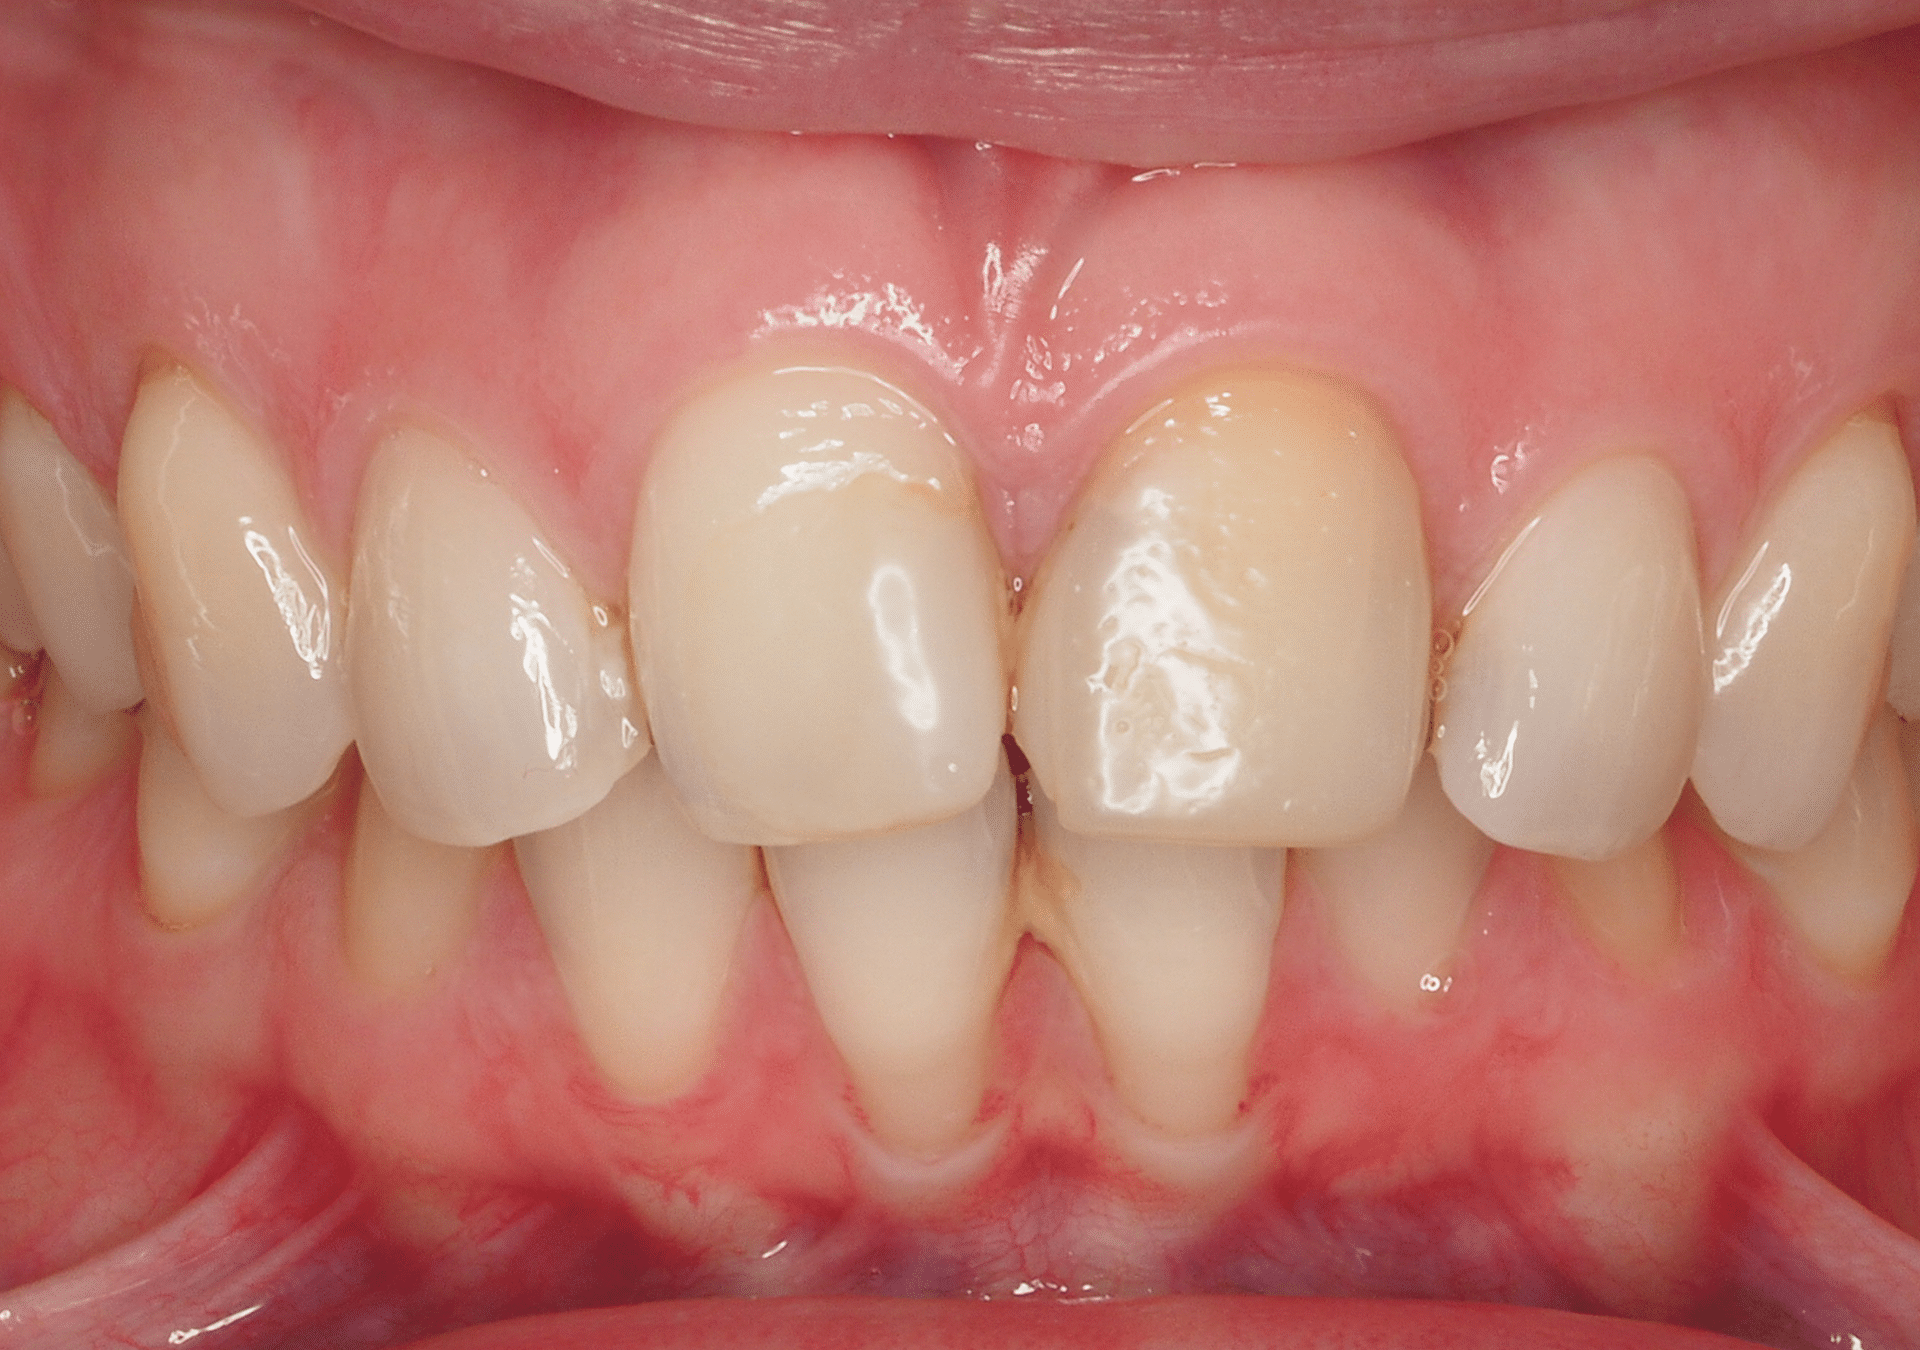

- Protocolo del doctor Josep Lluís Padrós actualizado con aplicación mixta domicilio/clínica, con resultados exitosos el 100% de los casos.

- Técnicas de blanqueamiento eficaces en casos difíciles, incluidas las tinciones por tetraciclinas.

- Tratamiento confortable y de gran durabilidad, sin alterar la estructura dental